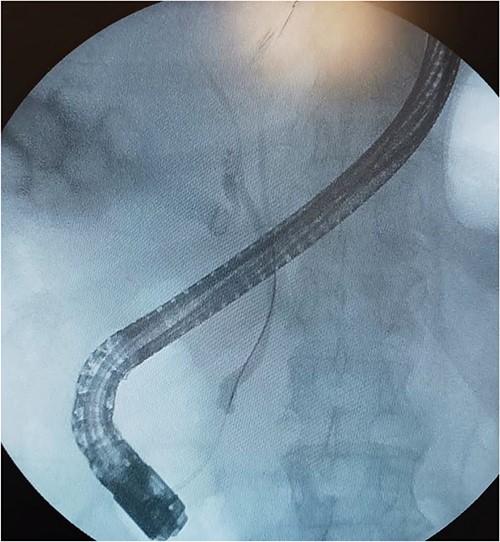

A 61-year-old Mexican man presented to the emergency room with an epigastric pain; he was admitted due to acute pancreatitis of biliary origin and intermediate risk of choledocholithiasis. We performed a magnetic resonance reported, right posterior hepatic duct absence of signal, choledochal with presence of heterogeneous content with absence of signal in intrapancreatic portion of a choledochal duct (Fig. 1). On the endoscopic retrograde cholangiopancreatography (ERCP), a cystic drain of the RHD was found (Fig. 2). Patient presented slow clinical evolution with increased systemic inflammatory response syndrome for which a contrasted computer tomography was performed with findings of pancreatitis with Balthazar C score. Subsequently, an adequate evolution was presented, and the acute picture of pancreatitis is resolved, hospital discharge was performed to an elective laparoscopic cholecystectomy of interval.